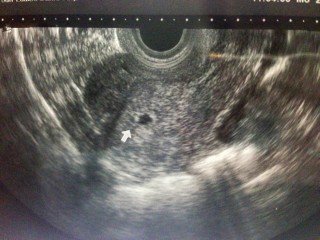

周期で計算をしたら5w0dでしたが本日初診に行ったら「4w5dぐらいかな?」と言われました。赤ちゃんの袋も多分これ…と。 前回、流産をしてるので心拍が確認出来るまでは物凄く不安ですが無事に育ってくれる事を祈ってます。また一週間後に受診予定です。

袋が見えた瞬間感動しました♥ 中にうっすら見えるのが赤ちゃんかな?

はっきりした週数は言われませんでしたが4週目後半とのこと。まだ5.7mmでしたがしっかりと胎嚢確認とれました!次の受診は2週間後です(^^)